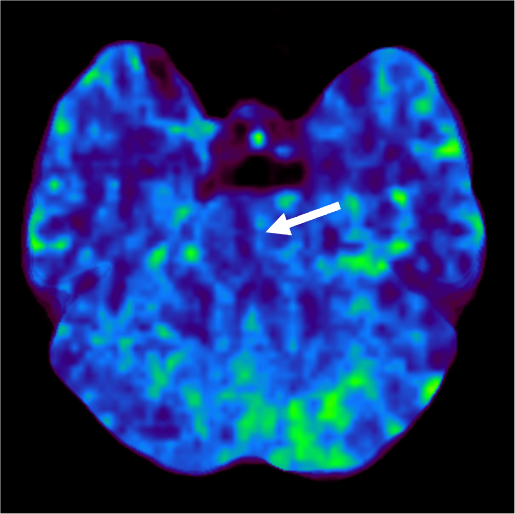

発症5日目に脳血管評価目的でCT angiographyの撮像依頼あり。MRI撮像ができないため、脳梗塞評価も兼ねて、全脳の多時相CT angiographyを撮像し、同一の収集データからCT perfusion画像も評価した。TIAの臨床診断であったが、単純CTとCT perfusionの所見から急性期~亜急性期ラクナ梗塞と診断した。

当該疾患の診断における造影CTの役割

急性期脳梗塞に対する血栓回収療法の適応判断においてCT perfusionの有用性が報告されている1-3)。CT perfusionは迅速にTmaxやCBFなどからischemic coreやpenumbraの評価が可能であり、また自動解析ソフトを用いることで客観的な定量評価が可能となる。320列CTで撮像すると、同じ撮影データから最適なCT angiographyやCT venography、多時相CT angiographyが再構成可能であり、脳梗塞の機序評価や血栓回収療法の治療戦略決定において有用である。本症例のようにMRI禁忌患者においては特にCT angiographyやCT perfusionが有用であった。